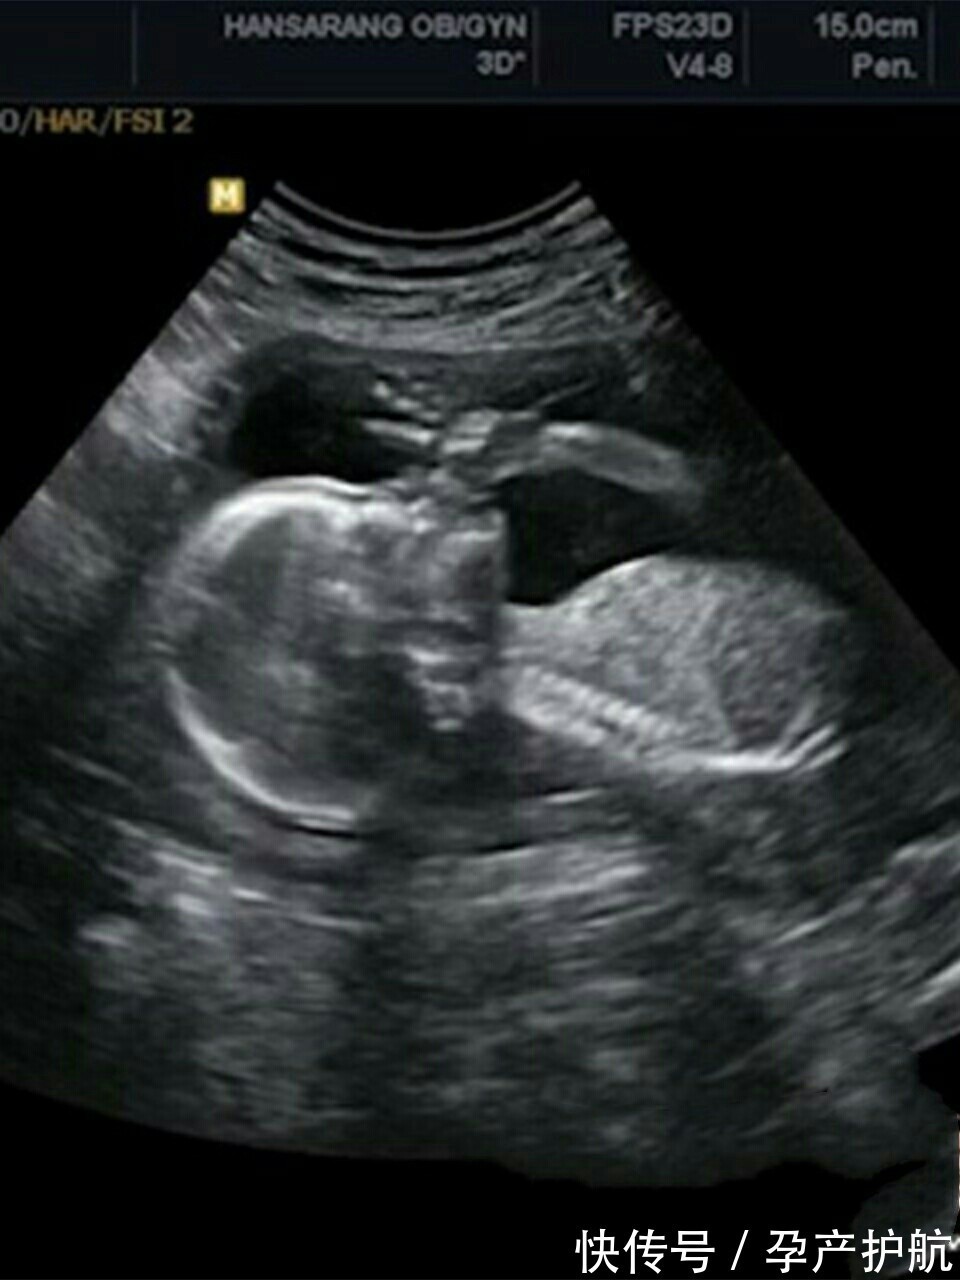

- 四维彩超|孕期最关键的4次产检,就算再忙,宝爸也要陪孕妈一起